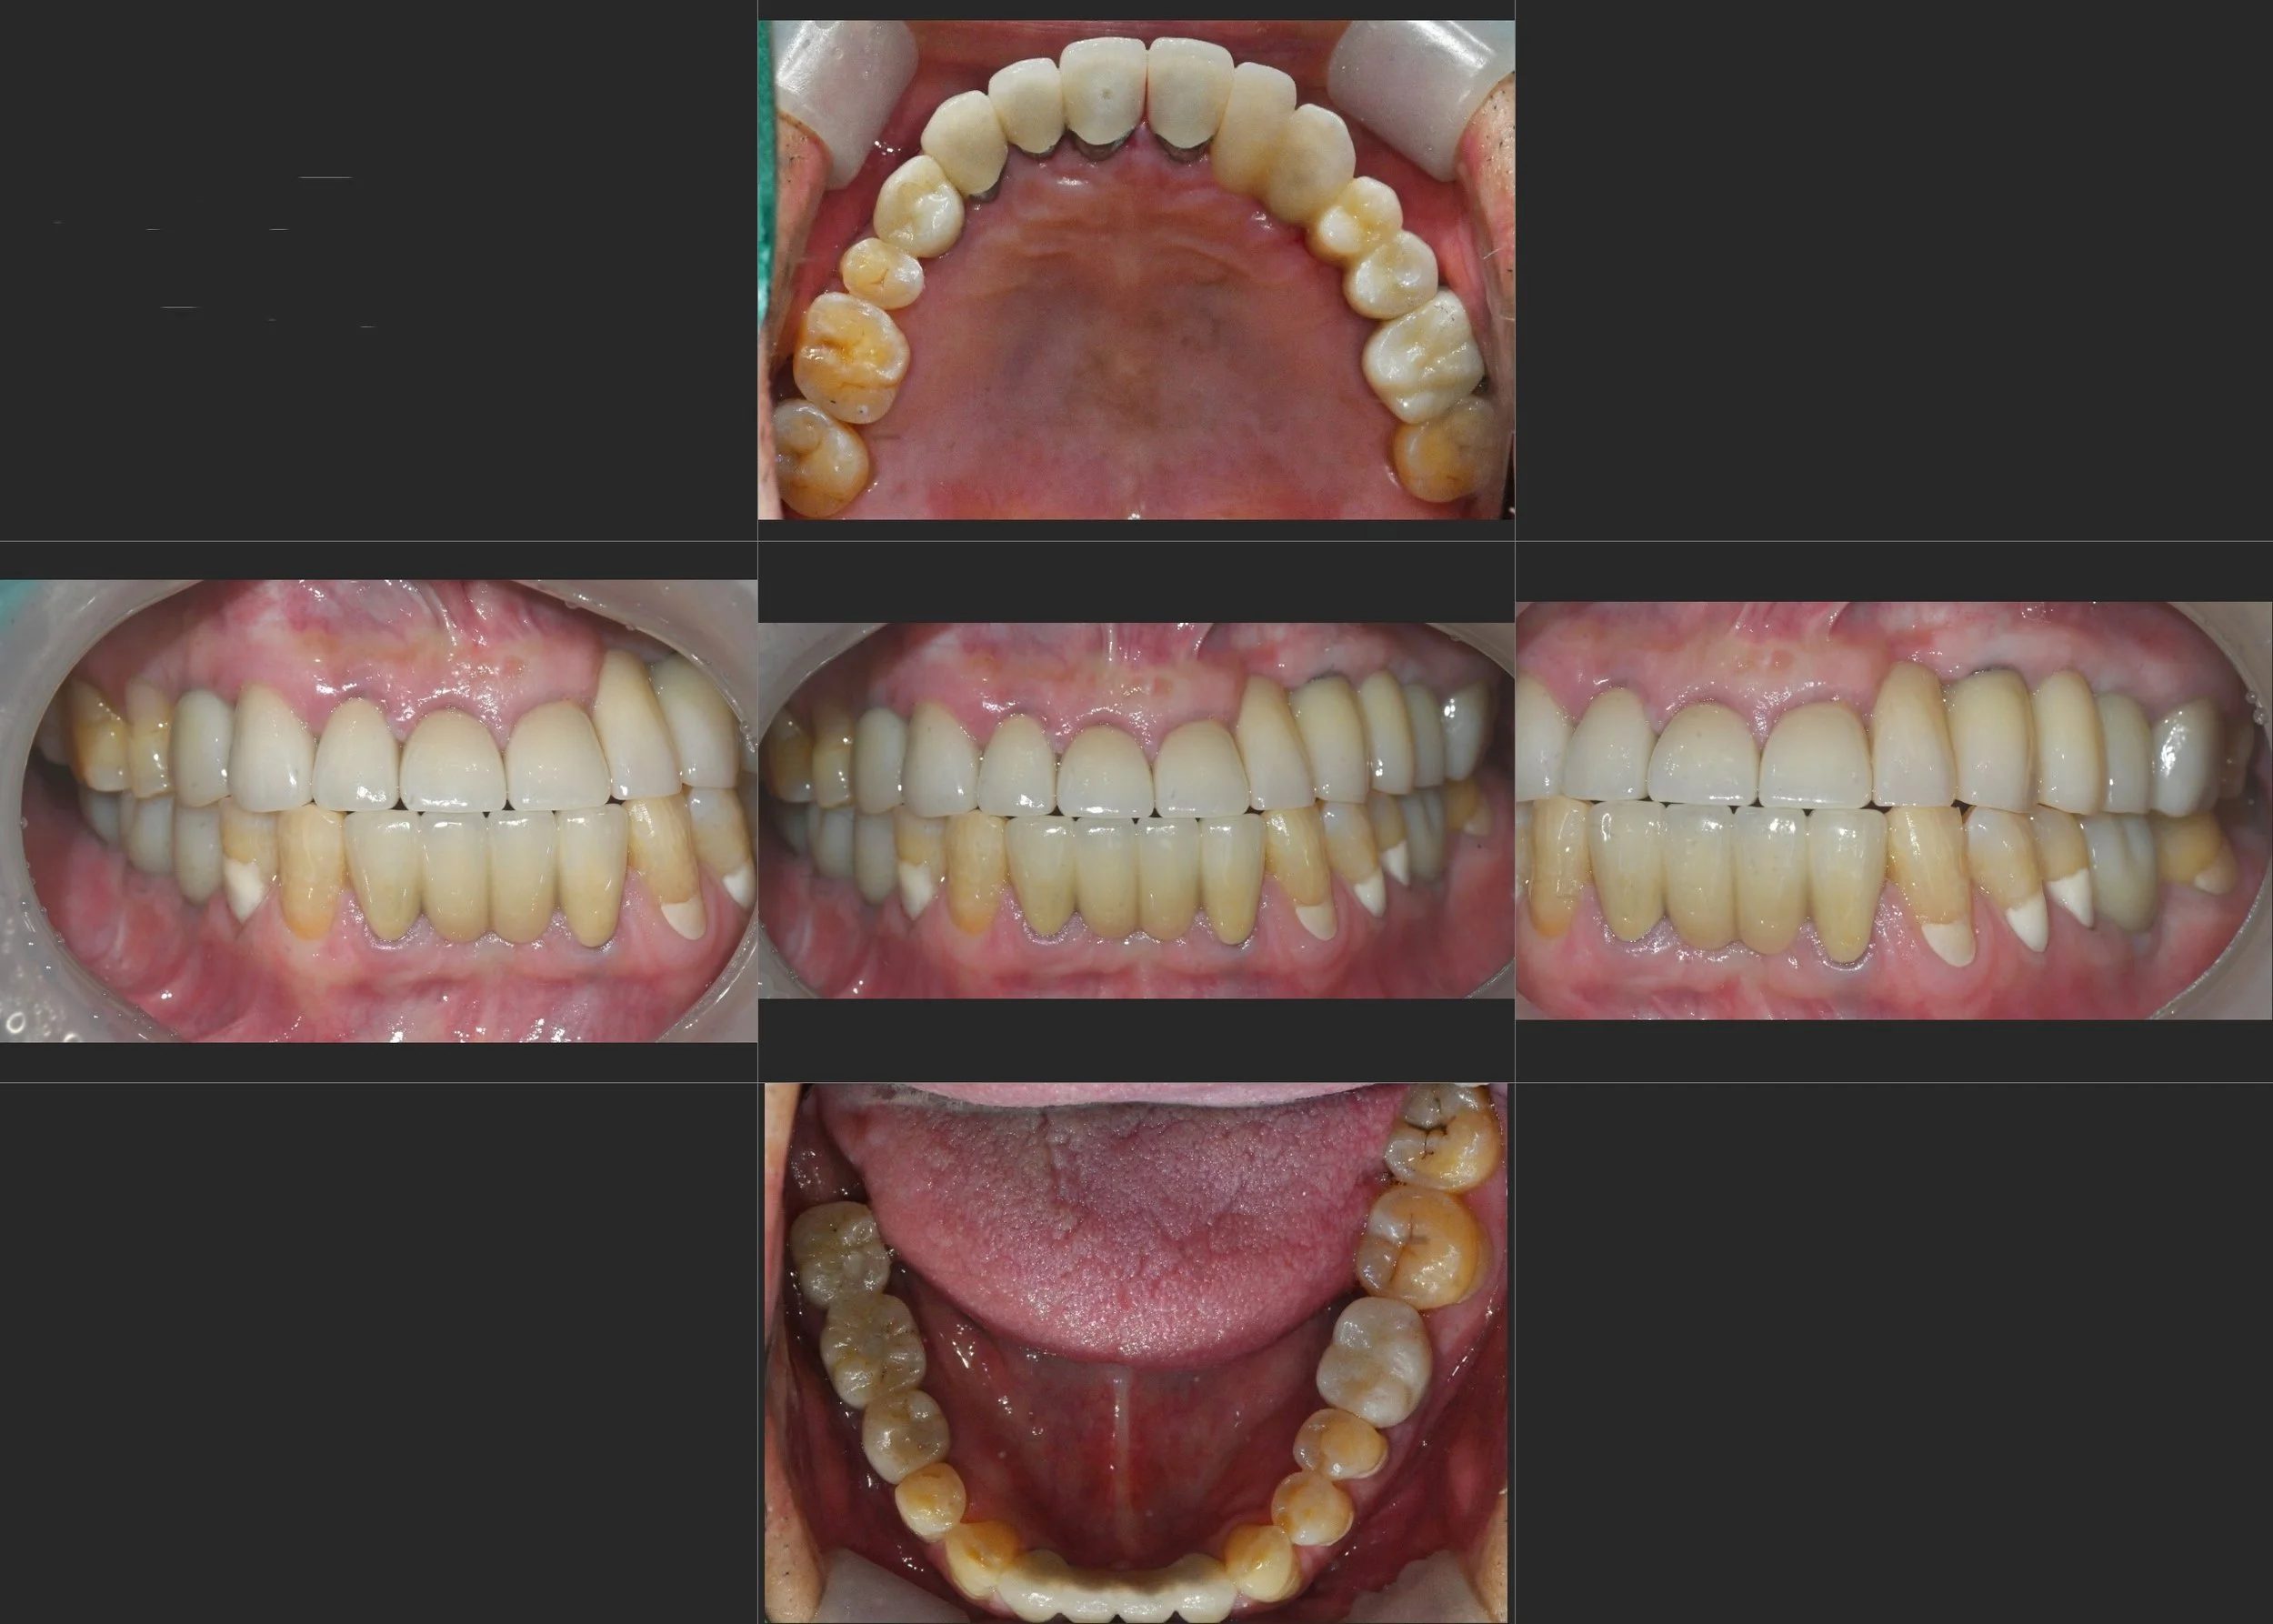

INTRA ORAL - AFTER

3. Edge-to-Edge Reconstruction: Due to the inherent skeletal Class III discrepancy, achieving a standard Class I overjet was not feasible. Instead, the final prosthetics were designed to meet in an edge-to-edge relationship. This approach provided maximum functional stability while preventing future prosthetic fracture.

4. Aesthetic Outcome: The final delivery of the full-arch restorations significantly improved the lip support and restored the lower facial height, resulting in a dramatic rejuvenation of the patient's facial profile.

The patient experienced a successful transition from a functional and aesthetic failure to a stable, fixed rehabilitation that he can now maintain with confidence.